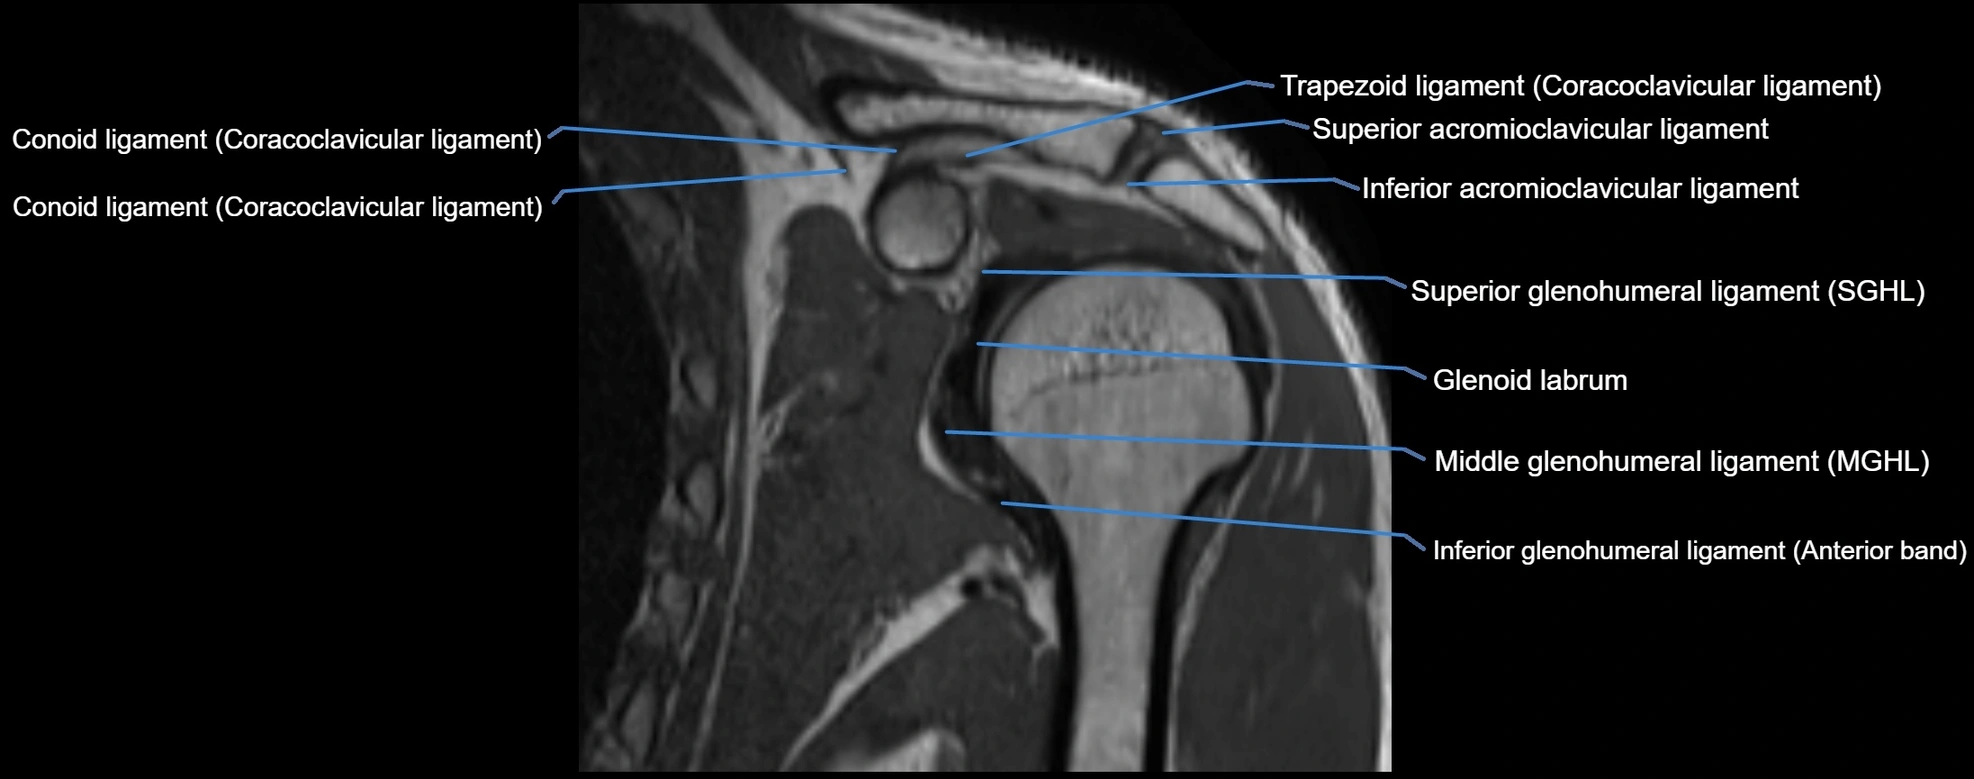

CT image

image